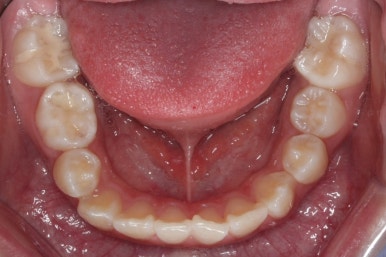

아래쪽에도 이제 장치를 전부 부착했습니다.

한 쪽의 송곳니는 제위치로 벌써 자리를 잡았네요.

장치를 부착한 후에 순차적으로 변화가 나타나는 모습입니다.

총 4장의 사진 동안 경과한 시간은 불과 6개월 입니다. 헤드기어를 통해 사전에 작업을 해뒀기 때문에 이후 연산동덧니교정 과정은 편해진 것이죠.